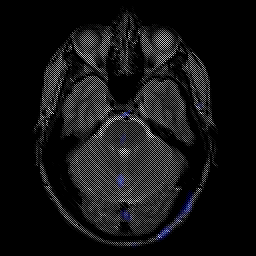

glioma overlay -- Slice #8

[Home][Help][Clinical] Slice 8